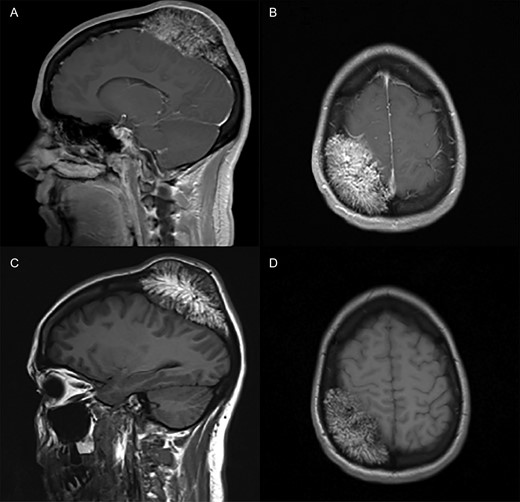

MRI revealed a lesion centered within the right parietal bone extending to the cranial vertex with corresponding calvarial expansion into the extra-axial space over the right posterior-frontal and parietal lobes with resultant cerebral compression (Fig. 2). There was no radiographic evidence of osseous destruction or parenchymal edema. There were no other intra- or extra-axial lesions identified. The decision was made in conjunction with the patients’ wishes to proceed for surgical resection.

T1-weighted magnetic resonance with sagittal (A) and axial (B) views provided. Imaging demonstrates the presence of an extra-axial mass expanding the calvarium and exerting mass effect on the right parietal lobe without the presence of aggressive destruction. The mass does not demonstrate contrast-enhancement as noted in sagittal (C) and axial (D) views after contrast administration. The underlying parenchyma does not demonstrate any reactive signal changes.